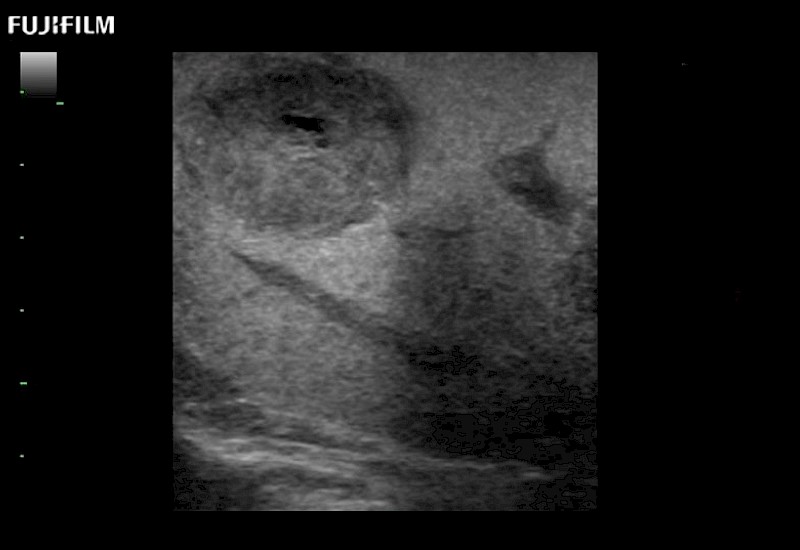

Learn moreFujifilm Healthcare continues to listen to the experts, our neurosurgeons, by developing an ultrasound system specifically designed for the Operating Room.

Guidance is the fundamental purpose for all of our surgical ultrasound technology. Fujifilm Healthcare is committed to designing tools that help neurosurgeons navigate inside the human body and provide the necessary information to immediately make critical surgical decisions.

With the ARIETTA Precision the next level of surgical ultrasound is here.